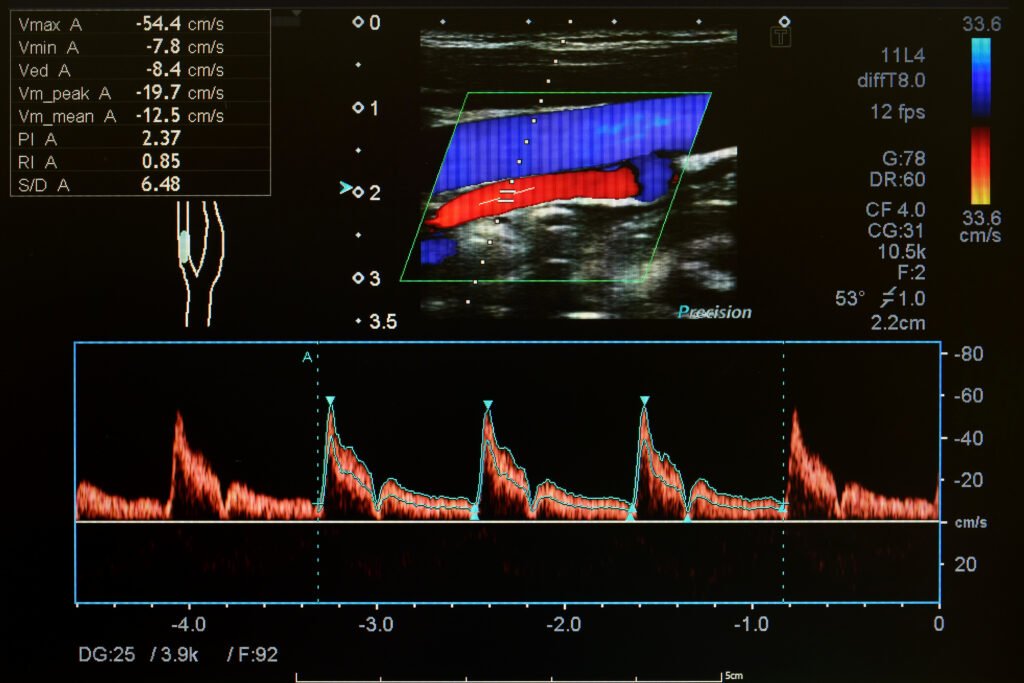

Doppler Ultrasound. Doppler ultrasound is used to assess blood flow through the veins and arteries. It can detect abnormalities such as blood clots, blockages, or narrowing in the blood vessels. This test is commonly used to diagnose conditions like deep vein thrombosis (DVT) or varicose veins.

Who should have it? Those experiencing symptoms such as leg pain, swelling, or changes in skin colour may need this test. It’s also helpful for monitoring patients with known vascular conditions.